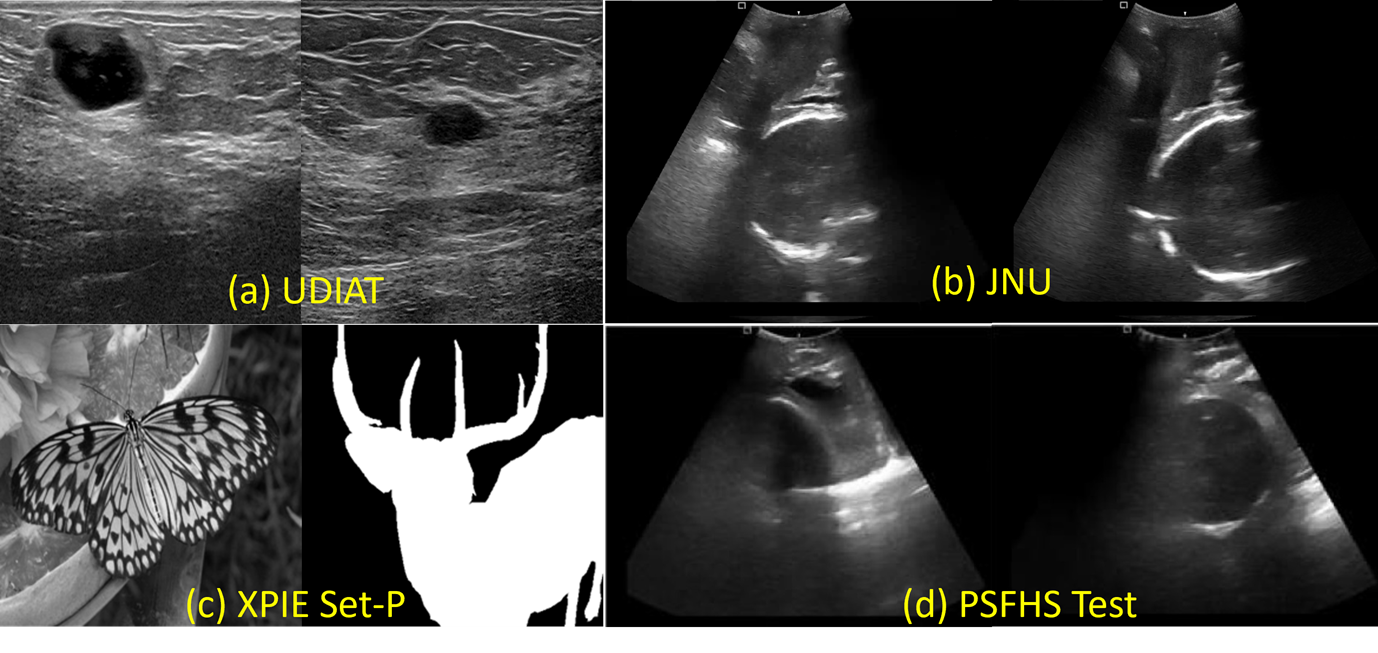

Refer to caption

Figure 4: Sample images from datasets: (a) UDIAT, (b) JNU-IFM, (c) XPIE Set-P, and (d) PSFHS Test.

We evaluate the proposed method using three public datasets for training/validation and one benchmark dataset for downstream segmentation. Unless noted, all images are used in grayscale B-mode.

• UDIAT Dataset B [28]: Breast ultrasound dataset with tumor annotations, collected at the UDIAT Diagnostic Center, Spain, using a Siemens ACUSON scanner. The average image size is 760×570760\times 570 pixels. Publicly available at https://helward.mmu.ac.uk/STAFF/m.yap/dataset.php. Samples used: 131 (train), 16 (val), 16 (test).

• JNU-IFM [20]: Intrapartum fetal monitoring dataset with grayscale 2D transperineal ultrasound scans. It contains 6224 images extracted from 78 videos of 51 patients, acquired using a Youkey D8 wireless probe. Labels were validated by expert radiologists. Available at https://figshare.com/articles/dataset/JNU-IFM/14371652. Samples used: 4224 (train), 1000 (val), 1000 (test).

• XPIE Set-P [27]: Natural images with ground-truth masks used to expose the model to cross-domain textures and to synthesize phantom-like inputs during degradation modeling. Available at http://cvteam.net/projects/CVPR17-ELE/XPIE.tar.gz. Split: 850 (train), 200 (val), 200 (test).

• PSFHS [5]: Intrapartum transperineal ultrasound annotated for pubic symphysis and fetal head; image size 256×256256\times 256 pixels. Access upon request via https://ps-fh-aop-2023.grand-challenge.org/. Split used in this work: 3200 (train), 800 (val), 700 (test). Important: The PSFHS train/val splits are used only to train the downstream UNet segmentation model; the proposed denoising model is not trained on PSFHS. The 700-image test split is held out exclusively for reporting segmentation with/without our preprocessing.

Sample images from each dataset is shown in Figure 4.